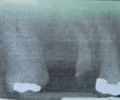

identify the error

elongation